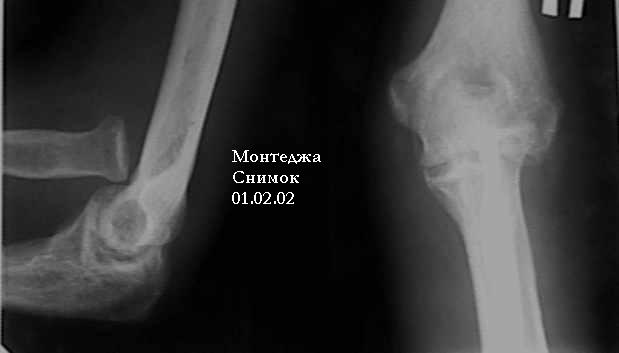

У больного травма в октябре 2001. Перелом Монтеджа разгибательный.Проведена операция металлостеосинтез пластиной, винтами локтевой кости. Вывих головки лучевой кости не диагностирован. В конце февраля 2002 г снята гипсовая повязка. Имеется ограничение сгибания до 115 градусов. Больной обратился в наше лечебное учреждение 07.02.02. Мы предложили ему оперативное лечение. Планируем провести резекцию головки лучевой кости. Есть мнение попытаться вправить головку лучевой кости, провести пластику кольцевидной связки, фиксисировать головку лучевой кости трансартикулярно спицей. Но боюсь, что в момент остеосинтеза была укорочена локтевая кость, поэтому необходимо будет провести резкцию в области диафиза лучевой кости, а затем провести остеосинтез лучевой кости. Рентгенограммы:

1; 2; 3; 4

Учитывая, что мы имеем опыт хороших функциональных результатов после резекции головки лучевой кости при оскольчатых переломах головки лучевой кости, мы ограничились проведением резекции головки.